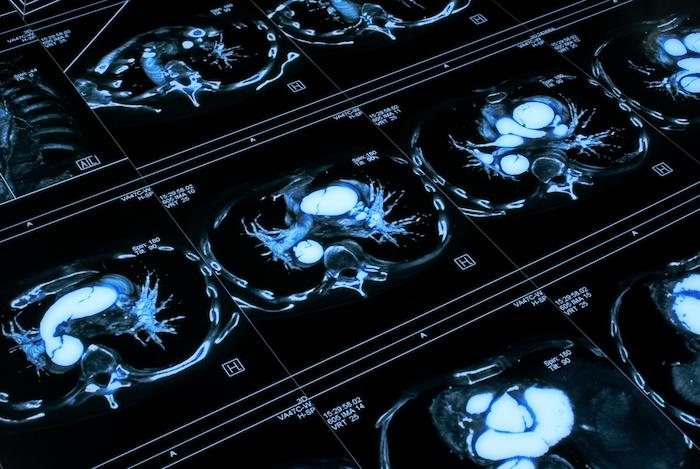

Leurs travaux font état d’un risque 66% plus élevé de développer un anévrisme (dilatation) ou une dissection (rupture) de l’aorte. Durant les 60 jours suivant l’instauration du traitement, il y a eu 64 cas d’anévrisme ou de dissection aortique parmi les 360 088 personnes traitées par fluoroquinolones, contre 40 cas sur 360 088 individus traités par amoxicilline.